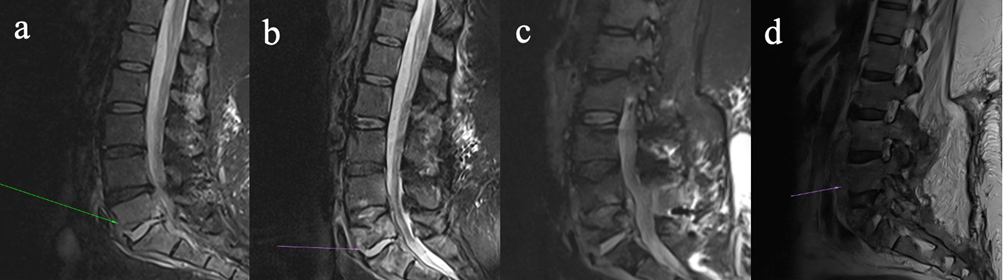

Figure 2Four-panel figure demonstrating progressive discitis/osteomyelitis involving the lower lumbar spine on magnetic resonance imaging (a–d). (a) Sagittal STIR images show discitis/osteomyelitis at L5/S1. (b) Sagittal STIR images now demonstrate progression of disease, with erosion of the L5 superior endplate, development of an anterior epidural collection, and associated ligamentum hypertrophy with resultant bunching of the distal cauda equina. (c) STIR image pre-instrumentation removal demonstrate a progressive discitis/osteomyelitis at L4/L5, with multiple enhancing collections within the anterior epidural space and posterior to the anterior longitudinal ligament. (d) Sagittal T2 images of the lumbar spine post-hardware removal demonstrate further destruction of the L5 vertebral body, with a persistent enhancing collection within the anterior epidural space, and a new collection along the anterior longitudinal ligament.

She re-presented 3 weeks later with pyrexia, drowsiness, and progressive lower back pain. A repeat MRI lumbar spine revealed L5/S1 osteomyelitis with bilateral multiloculated abscesses involving the iliopsoas muscles (Fig. 2a). Interventional radiology facilitated a biopsy of the L5/S1 disc space which identified M. abscessus complex. Peripheral blood cultures identified Mycobacteria species other than tuberculosis complex. Antimicrobial therapy (Fig. 1) was commenced with amikacin, linezolid, tigecycline, and meropenem, since imipenem and cefoxitin are not widely available in Ireland. Following multi-disciplinary discussion, surgical intervention was deferred as it was deemed high-risk given the absence of neurological symptoms. Based on drug susceptibility testing (DST) (Table 1), azithromycin and clofazimine were added to the regimen and linezolid was discontinued. Meropenem was stopped due to a suspected delayed hypersensitivity reaction. Following 3 weeks of antimicrobial treatment, repeat mycobacterial blood cultures were sterile.

Six weeks after starting antimicrobial treatment, she developed new loss of power in ankle dorsiflexion. A repeat MRI lumbar spine revealed an anterior epidural abscess at L4/L5, narrowing of the spinal canal, and bunching of the cauda equina (Fig. 2b). The acute cauda equina syndrome prompted emergent surgery for decompression and stabilization with pedicle screws and rods. Intra-operative tissue samples identified Mycobacteria species other than tuberculosis complex. Her dose of prednisolone was doubled to 30 mg prior to surgery as a stress dose which was tapered postoperatively. She completed induction antimicrobial regimen during her 4-month admission, and was discharged on azithromycin, clofazimine, and bedaquiline (Fig. 1).

At Infectious Diseases clinic follow-up, she endorsed worsening back pain and new skin lesions. A biopsy of the skin lesions showed acid-fast bacilli (AFB) on stains and isolated Mycobacterium abscessus complex (Table 1). Repeat MRI lumbar spine (Fig. 2c) displayed an increase in the paraspinal subcutaneous fluid collection (5.0×2.2×13 cm), but repeat mycobacterial blood cultures showed no growth. Amikacin and tigecycline were restarted, and the patient was transferred to the National Spinal Unit for surgical evaluation. Upon transfer, she underwent surgical debridement and washout with removal of spinal metalwork to achieve source control. Intra-operative samples showed AFB on smears, and M. abscessus complex was identified on culture (Table 1) and whole genome sequencing (WGS); however, subspeciation could not be performed.

Her postoperative course was complicated by severe pancreatitis, requiring admission to the intensive care unit (ICU), which led to the discontinuation of tigecycline and bedaquiline, tapering of prednisolone, and the addition of cefoxitin. Due to the limited antibiotic options for M. abscessus, the isolate was sent to a research laboratory in Cleveland Veteran's Affairs (VA) Medical Center, Ohio, United States of America, for β-lactam synergy DST. To decrease net immunosuppression, prednisolone was tapered to 10 mg d−1. Following discharge from ICU, she developed new skin nodules on her extremities, a biopsy of which showed necrotizing granulomatous inflammation; however, mycobacterial culture of the biopsy was negative and blood cultures were negative. Repeat imaging revealed multiple paraspinal collections concerning for abscess (Fig. 2d). No other sources of infection were identified throughout the hospitalization. Once imipenem was available, cefoxitin was switched to dual β-lactam (DBL) therapy with imipenem plus ceftaroline (Fig. 1).